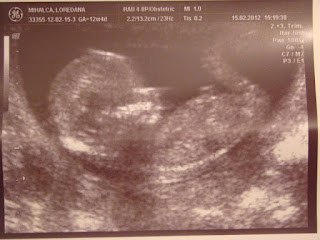

Știu că ai devenit amatoare de bloguri și că mai nou ai învățat să adaugi și comentarii. Mă bucur să văd că nu vrei să te oprești să înveți lucruri noi. Știu, de asemenea, că încă nu ai o căsuță de mail pe care să o verifici zilnic. De fapt ai, dar tu nu știi de ea și nu o folosești. Din acest motiv, m-am decis să îți scriu o scrisoare. În plic mai găsești o fotografie a celui/celei care va fi noul membru al familiei noastre.

Așa arată nepotul nostru care tocmai a împlinit, vreo, 12 săptămâni. Lui îi e bine. Atât mama, cât și tatăl lui au grijă de el. Tatăl lui este mai tot timpul bucuros. Bag de seamă că nu știe ce îl așteaptă. I-aș spune eu, dar realizez că nici eu nu știu. Cred totuși că îl așteaptă clipe frumoase. E tânăr și are putere să facă lucrurile așa cum trebuie. Încă nu știm sexul copilului. Deși nu prea contează, pare să se contureze un băiețel. Acum dacă o fi fată, noi tot vin roșu i-om da, cu cârnați afumați și gogoșari murați cu conopidă.